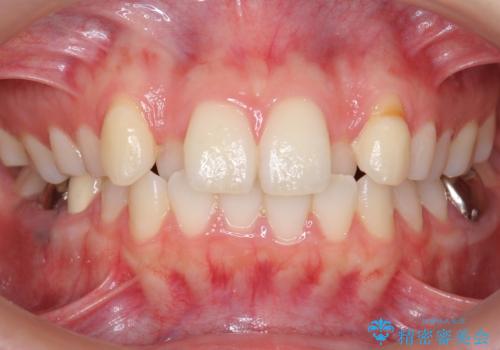

インビザラインで 抜歯矯正

- 20代女性

- 2年3ヶ月

- 前歯のがたつきを主訴に来院。

前歯が引っ込んでいると、そこが影になり大変目立ちます。

矯正治療で大きく見た目を改善することが可能です。